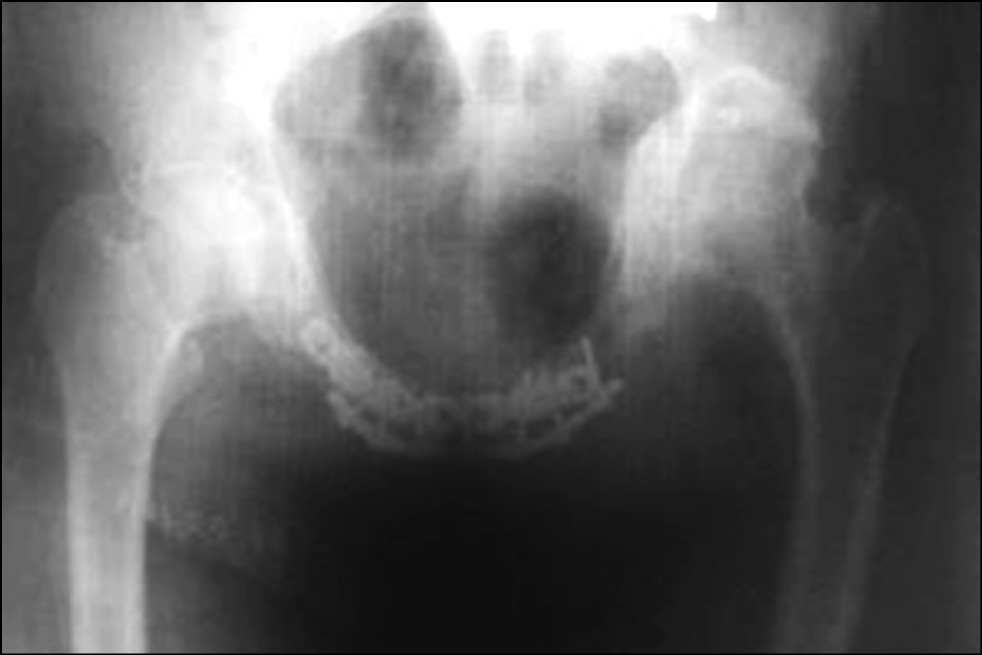

Через 34 дня пациент обратился на консультацию с жалобой на боли в переднем отделе таза. На рентгенограмме была выявлена дестабилизация металлоконструкции (рис. 3).

Рис. 3. Через 34 дня после операции

Fig. 3. 34 days after surgery

Использование методов фиксации, применяемых при острых травмах (до 3 нед. с момента травмы), в случае застарелых повреждений не позволяет достичь необходимых условий для стабильной фиксации. В первом клиническом примере отмечено, что при дестабилизации металлоконструкции диастаз между лобковыми костями вернулся к тому же уровню, что и при поступлении. Исходя из этого, мы приходим к выводу, что фиброзно-рубцовый процесс, сформированный в травматических очагах имеет стойкую, ригидную структуру, и при достижении анатомической репозиции таза с применением стандартного способа накостного остеосинтеза пластина испытывает более сильные механические нагрузки, чем в случае свежего повреждения, и происходит усталостный перелом металлоконструкции.